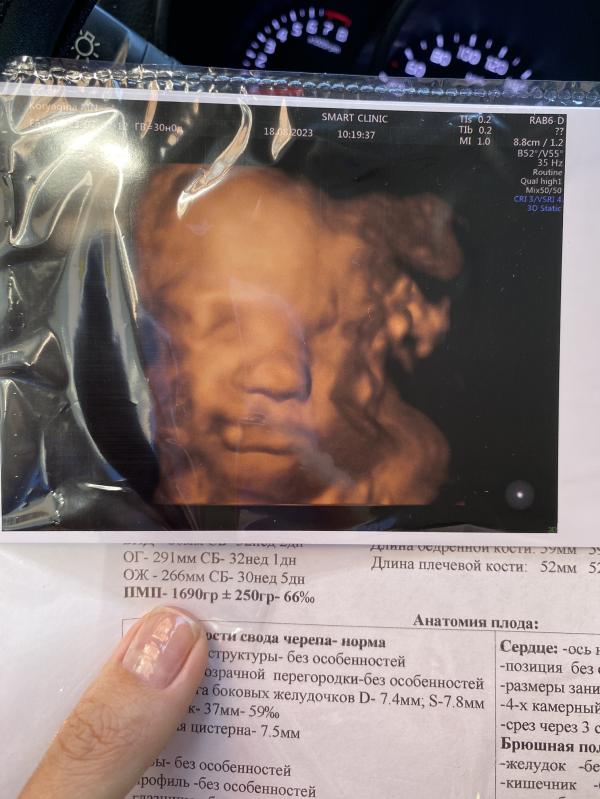

Что имеем:

Вес 1690 (+/- 250гр)

Развитие чуть опережает на 1-2 недели, но норма

Допплер отличный

Кровотоки в норме

Обвития нет

Головное предлежание

И еще у нас растут волосы 🤗